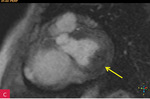

Rycina 7A-D. Obrazy rezonansu magnetycznego w osi krótkiej na wysokości pierścienia mitralnego: czarnej krwi T1-zależne TSE (A); czarnej krwi T2-zależne HASTE (B); T1-zależne echa gradientowego dynamicznie podczas podawania środka kontrastowego (C); sekwencja SSFP, pojedynczy obraz w osi krótkiej (D). W dolno-bocznej części pierścienia mitralnego od strony światła lewej komory zmiana (strzałki) niskosygnałowa we wszystkich ważeniach sygnału

W celu weryfikacji zmiany i oceny charakterystyki tkanki wykonano CMR,

w którym stwierdzono w dolno-bocznej części pierścienia mitralnego od strony światła lewej komory zmianę odpowiadającą morfologicznie CCMA, obejmującą 7,3 cm obwodu pierścienia mitralnego, o grubości w osi krótkiej do 25 mm, w osi długiej do 21 mm; zmiana ulegała brzeżnemu wzmocnieniu kontrastowemu i powodowała ograniczenie ruchomości tylnego płatka zastawki mitralnej, obejmowała struny ścięgniste mięśnia brodawkowatego tylno-przyśrodkowego. Ponadto uwidoczniono znacznie powiększone przedsionki z istotnym włóknieniem – jak w restrykcji (ryc. 7, 8).